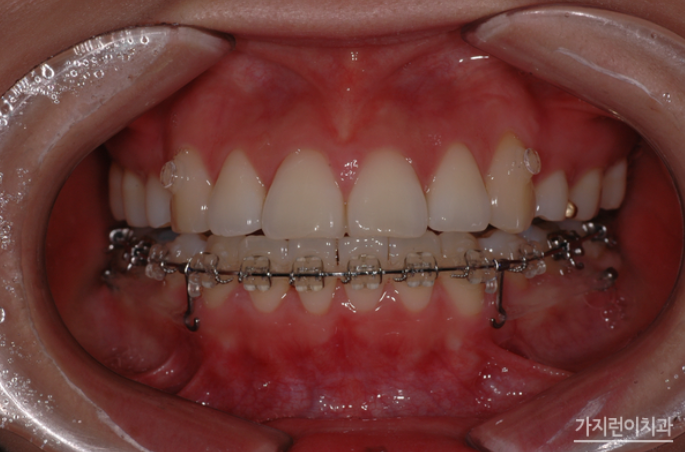

해당 환자분의 경우 잘 드러나 보이는 상악은 교정장치를 치아의 뒤에 부착하는 설측교정방식으로, 입술에 가려져 상대적으로 덜 부각되어 보이는 하악은 순측교정 방식으로 진행했습니다. 옥니를 교정하기 위해서는 치아를 이동시켜 다시 바깥 방향으로 각도를 조절해야 하기 때문에 충분한 힘을 받을 수 있도록 미니 스크류를 식립하여 교정용 고무줄을 연결했는데요. 상악 역시 앞으로 돌출되어 나온 부분을 뒤로 밀어 넣어야 하기 때문에 미니스크류를 식립하여 효과적으로 힘이 전달될 수 있도록 하였습니다.

이 사진은 치료가 끝난 후 모습입니다. 다소 흐트러졌던 치열도 가지런하게 배열되었고, 무엇보다 옥니 증상이 확연히 개선된 것을 확인할 수 있었는데요. 도드라져 보이던 상악 돌출도 만족스러울 정도로 개선된 모습을 볼 수 있습니다. 사실 돌출입은 안모 변화가 큰 편이라 살펴보지 않을 수가 없는 부분인데요. 재교정 전에는 상악 돌출로 인해 입이 잘 다물어지지 않았고, 입을 다물기 위해서는 입술 아래 턱에 힘을 주어야만 했다면 이후에는 자연스럽게 입이 다물어지고, 이상적인 측면 페이스라인을 확인해볼 수 있게 되었습니다.